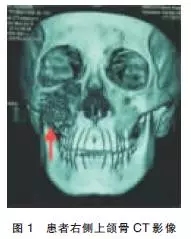

輔助檢查:2014-03-02在我院行CT提示右側(cè)上頜骨腫物,骨質(zhì)破壞明顯(圖1),于2014-03-07在全麻下行“右側(cè)上頜骨腫物探查術(shù)”。患者仰臥位,經(jīng)鼻插管全麻,常規(guī)消毒鋪巾,0.5%利多卡因+腎上腺素局部浸潤。于右側(cè)上頜前庭溝注射麻藥時(shí)回抽有血,改變進(jìn)針方向和角度仍回抽有血,遂用5mL注射器穿刺抽出約5mL新鮮血液,考慮血管瘤可能。于右側(cè)上頜骨前庭溝作一約2.5cm切口,暴露腫物呈囊狀切開骨膜后可見大量血液涌出,搔刮后未見實(shí)性瘤體組織,立刻嚴(yán)密縫合骨膜分層,縫合口腔黏膜。術(shù)畢,手術(shù)順利,麻醉滿意,手術(shù)歷時(shí)1h,出血量約100mL。

影像學(xué)診斷:①右側(cè)頜面部占位,血管瘤或惡性腫瘤可能;②垂體形態(tài)不規(guī)則,請結(jié)合臨床考慮(圖2)。于2014-03-18行“頸內(nèi)外動脈造影+血管瘤供血動脈栓塞術(shù)”,患者仰臥,心電監(jiān)護(hù)下,常規(guī)右腹股溝消毒,鋪無菌巾,2%利多卡因局麻后,以技術(shù)穿刺右股動脈,置入5F鞘管送5F單彎導(dǎo)管分別選擇性進(jìn)入兩側(cè)頸動脈。右側(cè)頸內(nèi)外動脈造影(圖3):右側(cè)頜面部可見富血供染色病灶,呈現(xiàn)“血管湖”徑,右側(cè)頜內(nèi)動脈為主要供血動脈,參與約80%供血,右側(cè)面動脈及顳淺動脈分支參與約10%供血,右側(cè)眼動脈分支參與約10%供血,左側(cè)頸內(nèi)動脈及各大腦動脈及其分支顯影清晰,未見明顯異常。